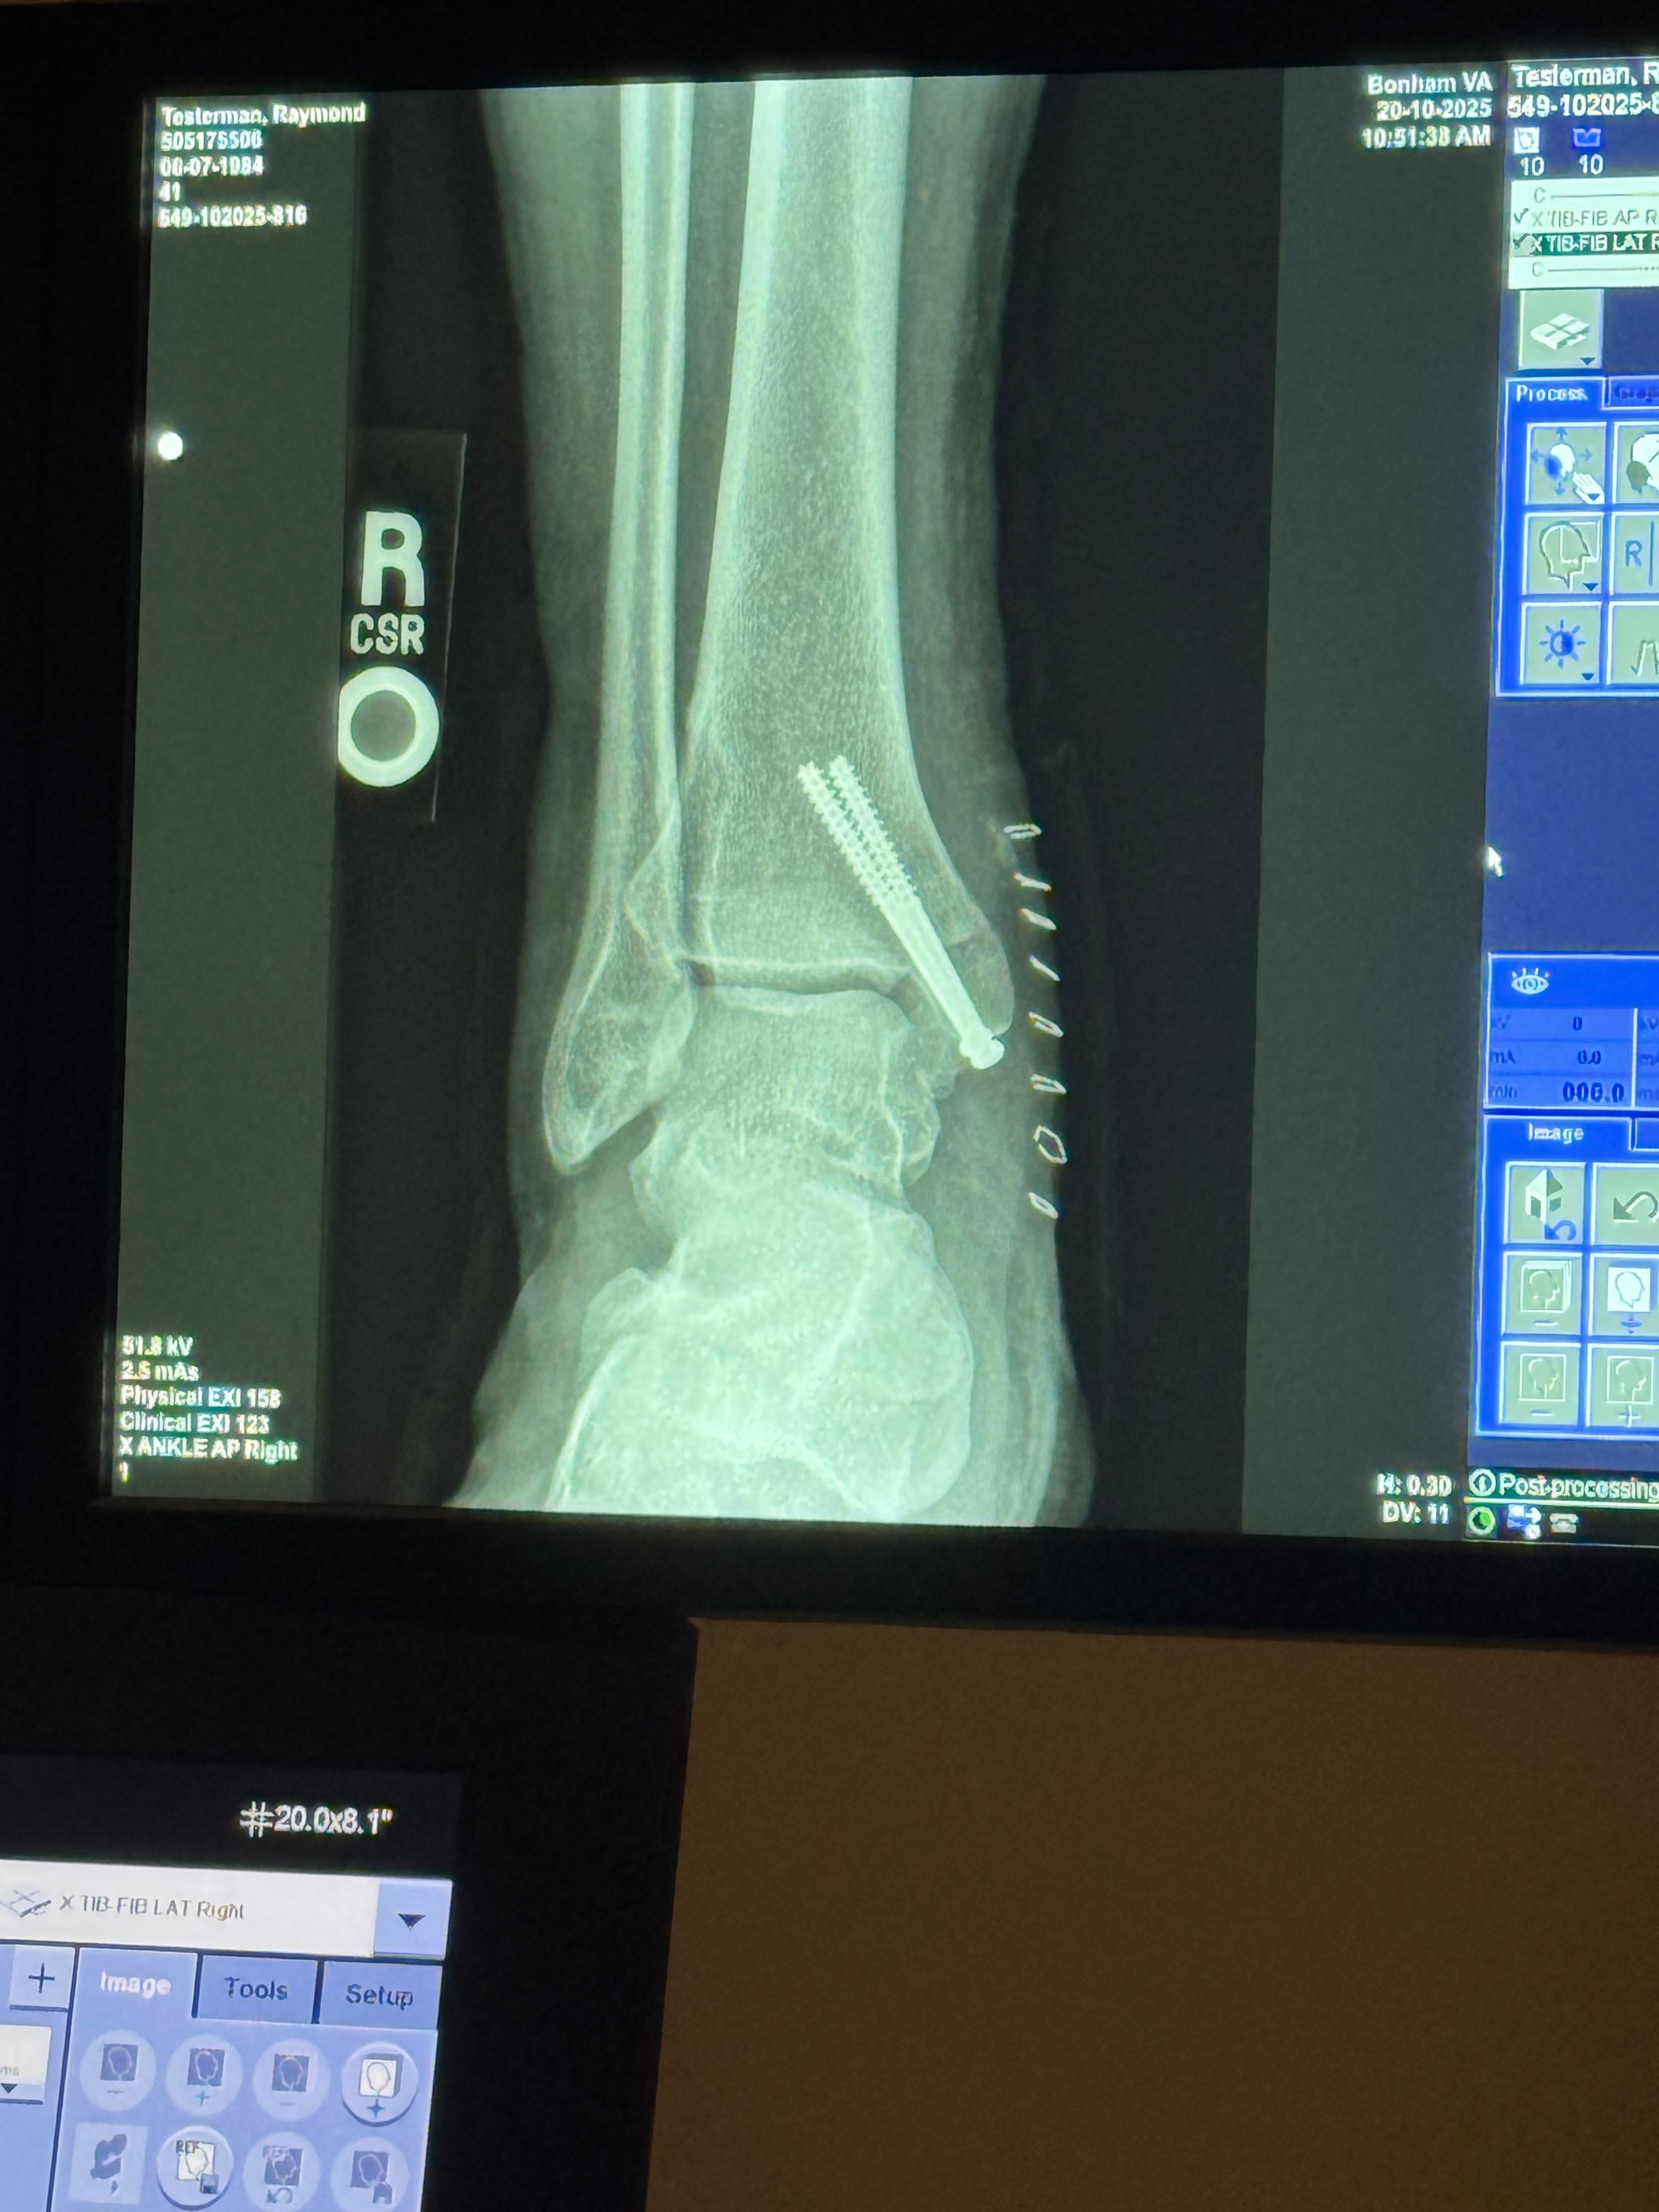

My name is Ray. I am a OIF & OIF2 veteranI who drove many miles on IED and ambush filled roads in Iraq back in 2004/5. Pity is not something I ask for and honestly, I'm very nauseous about even doing this, However, if it wasn't for my amazing wife and two amazing daughters, and the fact that I don't have a choice. That and our life is completely falling apart due to mother nature making things piling up. I can't seem to get a break on top of that, I am a 70% disabled veteran and still can't get help from the VA so Due to a deer taking me out on my motorcycle leaving me with a broken left tibia about an inch under the knee a severely dislocated broken ankle on the right leg with two screws in it I am no longer able to work at the moment. I'm going to lose my home my business but I know I won't lose my family because God is first and foremost, I am a truck driver by Trade actually an owner operator. My motorcycle insurance didn't even offer any kind of coverage to cover personal/professional expenses. i'm truly trying to keep my faith, but it's being whittled that more and more every day. I want you to know if you've read this far I am not looking for a handout but a hand up just a way to get on my feet if you have read this even the first two words, I pray God blesses you with abundance. I pray that he keeps you in his hand and never let anything happen to you and I pray these mighty things in the Lord and Savior son Jesus Christ name amen.